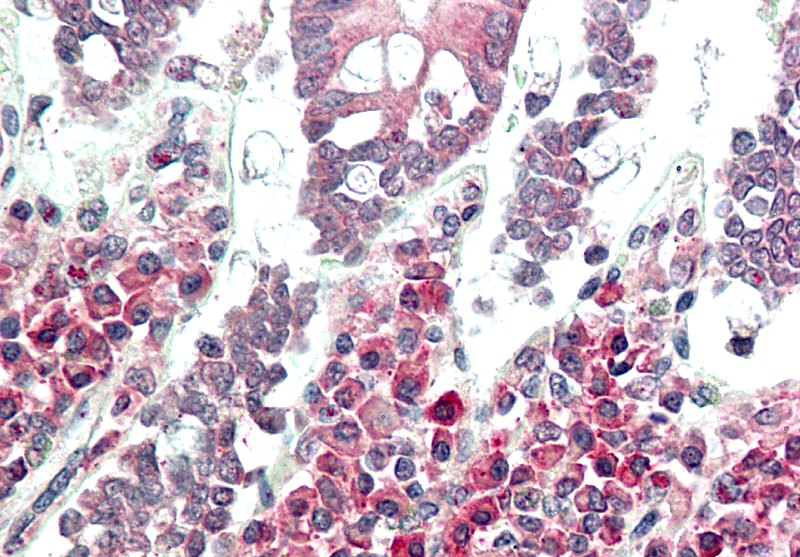

| Application: | FACS, IF, WB, IHC |

Western blot analysis: 2-4 µg/ml, FACS analysis: 0.5 µg/10^6 cells, Immunohistochemical analysis: 5 µg/ml